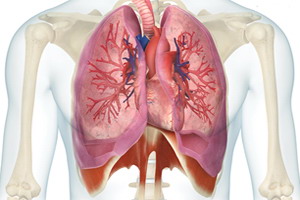

Alveoli polmonari

- Focolaio di Hamer: 5 e 21 del Tronco Cerebrale.

- Funzione: interscambio di diossido di carbono con ossigeno tra l'aria inspirata e il sangue che circola nei polmoni. Gli alveoli si gonfiano e si sgonfiano con inalazione ed esalazione. È necessario un certo sforzo per inspirare, dato che questi piccoli globuli devono essere insufflati, ma l'elasticità di questi globuli aiuta nel processo di esalazione. Se la retrazione elastica degli alveoli è compromessa, come nel caso dell'enfisema, la esalazione a forza diventa difficile. I polmoni sono composti di bronchi, bronchioli e alveoli. I bronchi principali i suddividono progressivamente e vanno diminuendo di diametro per divenire bronchioli. Gli alveoli polmonari sono strutture (sacchetti o globuli) globulari che formano grappoli alla fine dei bronchioli. Ogni polmone adulto ha circa 750 milioni di alveoli.

- Senso della Attivazione (Conflitto): panico della morte.

Paura arcaica e viscerale di non poter respirare, di morire affogato, di non poter digerire il boccone di aria (un tipo di paura della morte). - Fase Attiva: adenocarcinoma polmonare proliferante a cavolfiore (noduli), aumento dell'assorbimento di ossigeno.

- PclA: caduta drastica della funzione, caseificazione, infiammazione, congestione, bassa ossigenazione, dispnea, febbre, tubercolosi polmonare.

- Crisi epilettoide: espettorazione profusa, sanguinamento (emottisi non grave!

- PclB: infiammazione, normalizzazione della ossigenazione, sudori notturni.

- Normotonia: caverne, calcificazioni, noduli incapsulati compatti se non ci sono batteri.

Se il Conflitto è di paura di morire per se stessi, ci sono vari adenocarcinomi (noduli multipli).

Si il Conflitto è di paura di morire per altra persona o animale, c'è un solo adenocarcinoma (nodulo solitario).